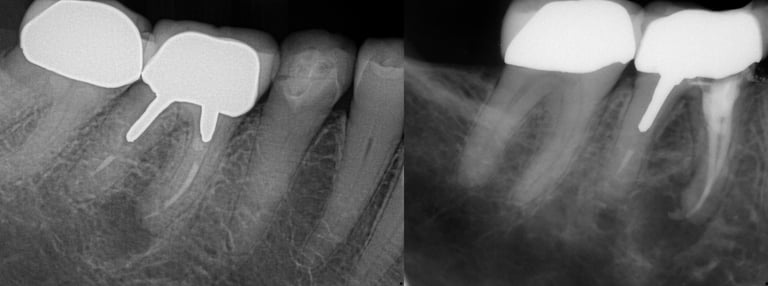

Gallery 2: Retreatment Cases

Retreatment Root Canal Cases with preoperative and postoperative radiographs.

#10 ReTx (original RCT poorly done)

#30 ReTx (original RCT had missed canal)

#14 ReTx (original RCT had missed 4th canal)